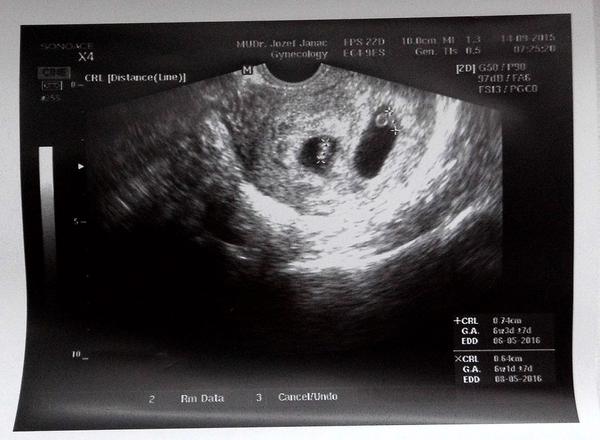

Ahoj, tak já nevím jestli sem patřím, ale třeba mi o tom něco řeknete...byla jsem v 5+4tt na kontrole u doktorky a na obrazovce utz byly takový dvě ťupky obalený černým kolečkem, byly dost u sebe, skoro tak že se černá kola okolo dotýkala- splývala, ale byla jsem tak mimo že jsem se na to nezeptala...a teď musím pořád myslet na to jestli to neznamená, že jsou to dvojčata, protože na to nejsem úplně připravená....

@mysliska Jee tak to uz mas za chvili 🙂 A kdy ti zjistili, ze mas dvojvajecne? Ja se vcera doktora v tom soku ani nezeptala, ale takhle podle fotky z utz bych rekla dvojvajecne, kdyz ma kazdy svou komurku. Nebo podle ceho se to pozna? Cisare sis zvolila ty nebo doktori? Ja bych rada sla prirozene pokud to bude mozne. Mam za sebou dva krasne pohodove porody, tak pokud budu mit dvojvajecne a vse bude v poradku, byla bych stastna za prirozeny porod. Z cisare mam strach. Hlavne si neumim predstavit, jak s tim odoperovanym brichem litam kolem dvojcatek a jeste dvou cacorek doma ☹

@mishkacz zjistili to v 9.tydnu myslim, i Tve vypadaji dvojvajecne, ale jsou pry i vyjimky, ze jsou treba jednovajecne a pak se takto rozdeli, takze stopro to nevi nikdo 🙂 dvojvajecne se teoreticky poznají podle toho, ze ma kazde ditko svou placentu a svou komurku a tak 🙂 cisar je u me bohuzel jasny kvuli me srdecni vade a i kdybych nemela tu vadu, doktor rika, ze je stejne jedna holcicka spatne natočena v brisku, lezi pricne, takze bych se cisari stejne nevyhla :( no bude to pro me novinka.